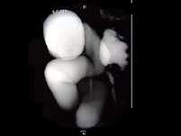

- 多项选择题女,28岁, 持续性腰痛加重2天,伴尿频、尿急、尿痛及发热, MRI如图所示,下列说法正确的是 ( )

A、单侧输尿管明显扩张,同侧的肾盂肾盏也扩张,但其程度轻于前者

B、考虑为先天性巨输尿管

C、考虑为输尿管下端结石并积水

D、考虑为输尿管癌所致的梗阻积水

E、考虑为输尿管囊肿